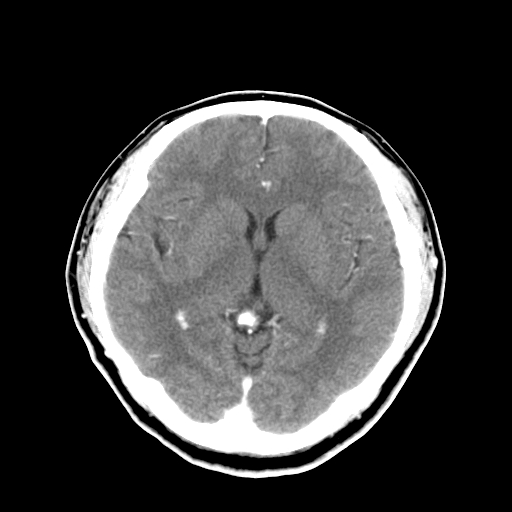

标题: CT16447B:(续)增强扫描图像。 [打印本页]

标题: CT16447B:(续)增强扫描图像。

患者今日做ct增强检查,现补传增强扫描图像。

松果体钙癍增大,无其他改变,定不了性

一般认为大于1cm为异常。